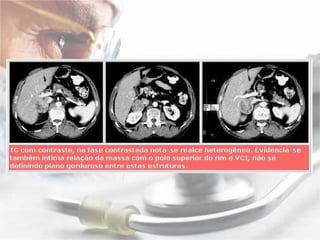

Localização:   A localização do feocromocitoma e feita com a utilização dos seguintes procedimentos radiológicos: tomografia computadorizada: com 85% a 95% de acuracia na localização de massas adrenais de ate 1 cm, não possibilitando a diferenciação entre feocromocitoma e metástases; ressonância nuclear magnética: que possui a capacidade de diferenciar feocromocitoma de adenoma ou carcinoma; mapeamento adrenal com I131 meta-iodobenzilguanidina (MIBG), de estrutura molecular semelhante a norepinefrina e que se concentra nas vesículas de estocagem de catecolaminas, possui 88% de sensibilidade, 100% de especificidade e 94% de acuracia na localização do feocromocitoma de ate 0,2 g de peso, de localização adrenal ou extra adrenal.